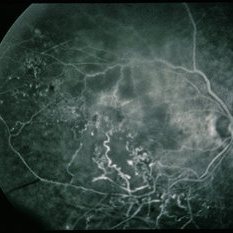

BRVO - Massive Exudate from Collaterals

Feb 24 2014 by David Callanan, MD

66-year-old female with BRVO - massive exudate from collaterals, 20/70 OD; 20/25 OS in 1985; +HTN, glaucoma; 20/200 OD 1987.

Condition/keywords: branch retinal vein occlusion (BRVO), collaterals, exudate